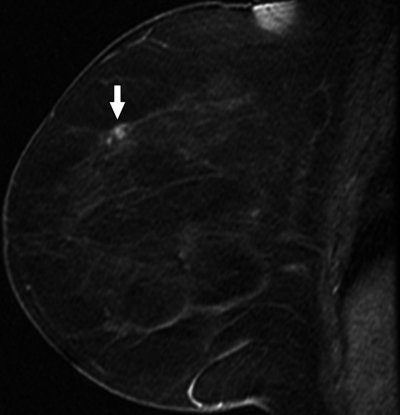

60-year-old woman with history of left mastectomy presents for follow-up MRI examination of right breast with normal mammogram and normal physical examination. Above, sagittal fat-suppressed image of right breast after contrast injection immediately before biopsy confirms presence of mass (arrow). Below, sagittal fat-suppressed image of right breast immediately after 9-gauge MRI-guided vacuum-assisted biopsy shows obturator (arrow) in high-signal hematoma obscuring biopsy site.